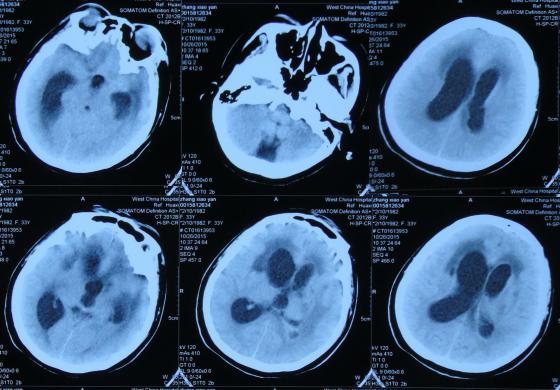

经头孢哌酮舒巴坦抗感染治疗1周后即2015年8月9日,仍间断头痛,发热有下降,但仍反复,但患者意识反变差,表情也变淡漠,查头部CT(图-2)。

图-2:2015年8月9日头部CT

第1家医院治疗13天后即2015年8月16日,查头CT:双侧侧脑室,三脑室及四脑室扩张(图-4),且给予腰穿检查,提示颅压高(脑脊液检查结果不详),给予相关对症治疗。

图-4:2015年8月16日头部CT

第1家医院治疗16天后即2015年8月19日,间断头痛,腰穿颅内压仍高,查头部CT示脑室进一步扩张(图-5)。

图-5:2015年8月19日头部CT